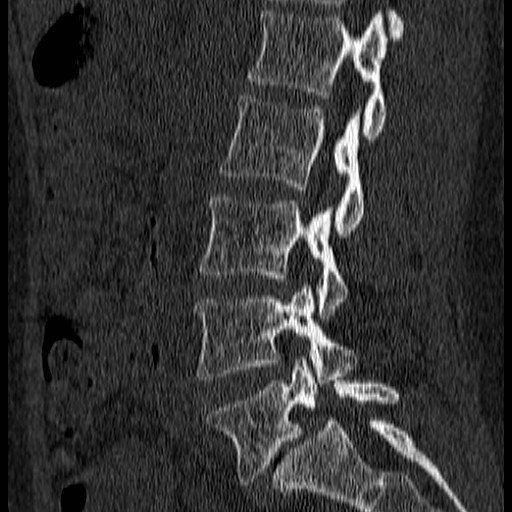

The images show how I treat a stress fracture of the lowest bone in the spine.

On this CT. The bones to the right of the image lie on top of each like roof tiles. The roof tile is disrupted in the lowest image because of a fracture (i.e a broken bone)

The disc space is seen to be distorted and the lower bone has changed to a white colour which can be a sign that this is causing pain.